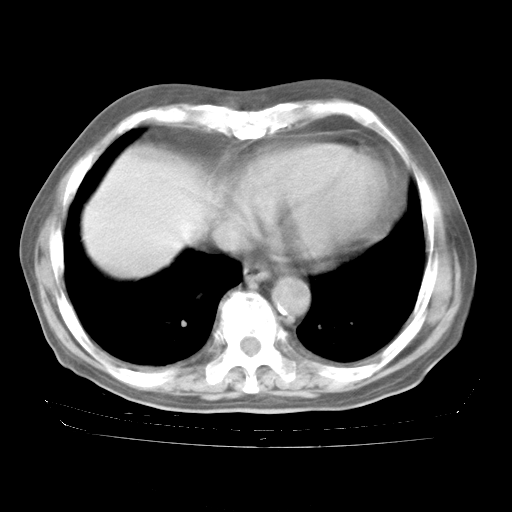

4月28日肺部CT——再次出现类似去年5月9日——透光度降低,“间质性”改变。

4月28日肺部CT